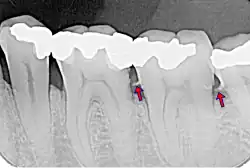

Según su localización, se distingue entre el sarro supragingival (amarillo), cuando se halla por encima de la línea de la encía, y el infragingival o subgingival (marrón), cuando se sitúa por debajo de esa línea.